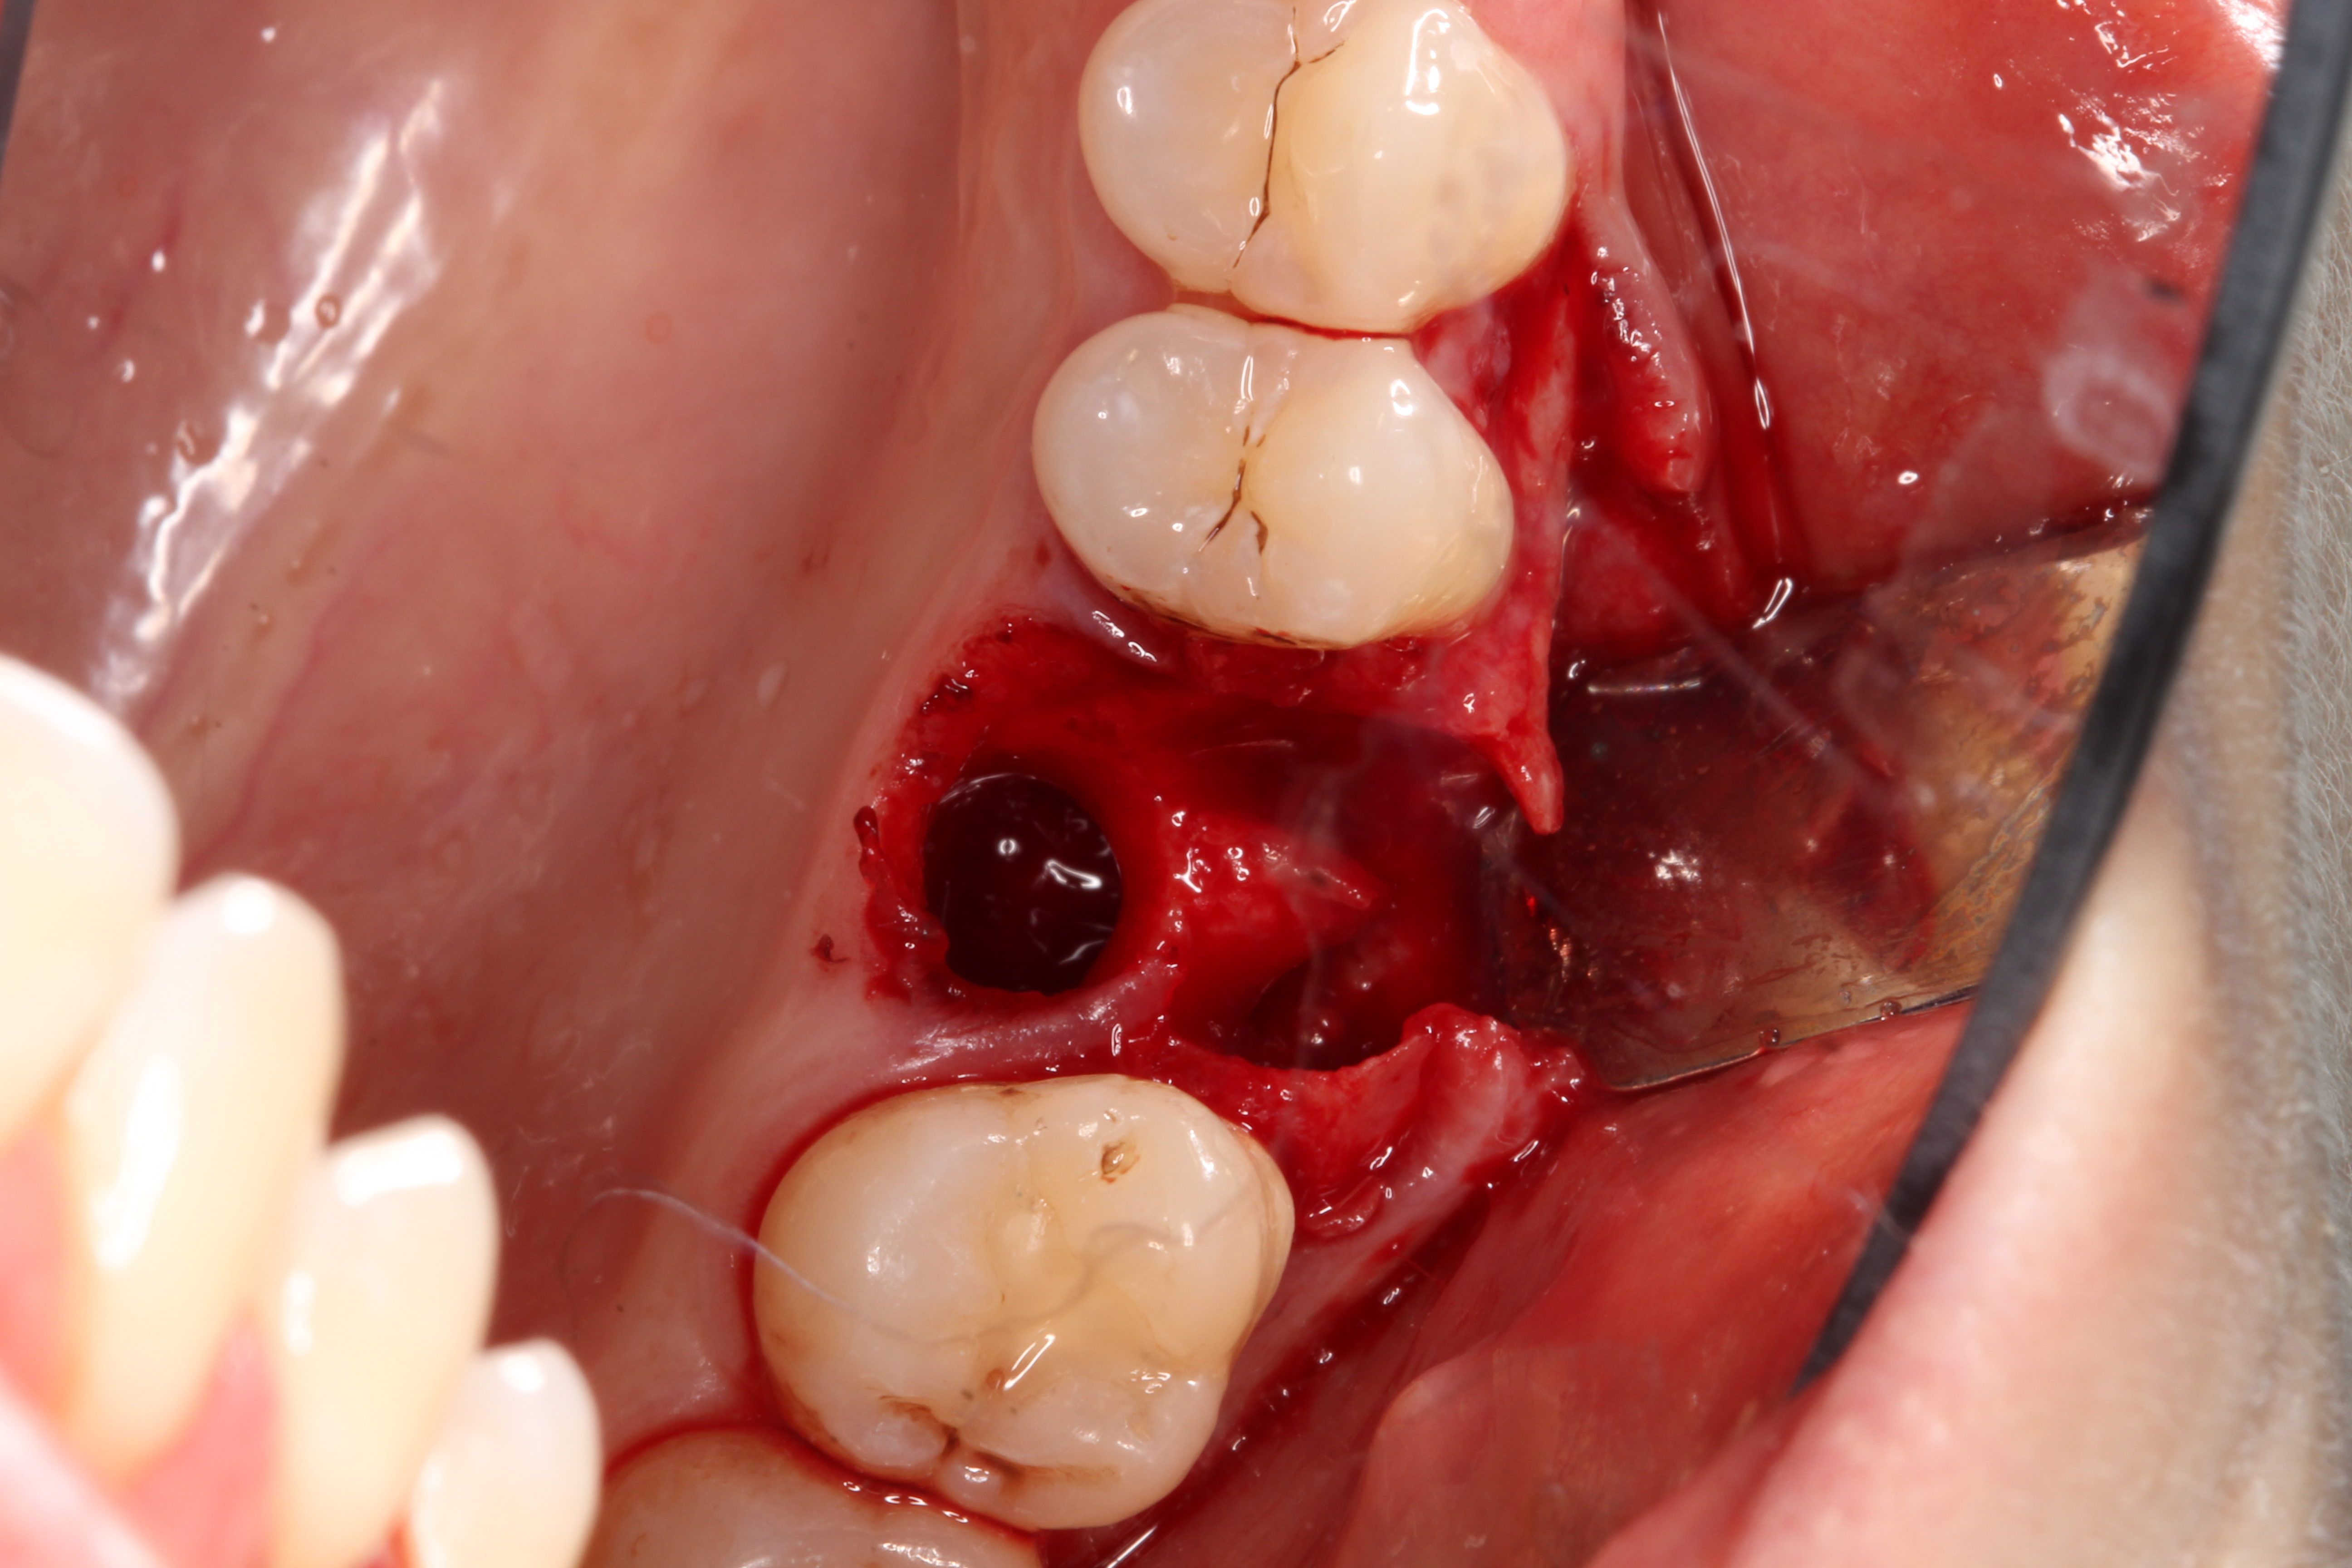

3. Make sure the socket is bleeding (Figure 6). If necessary, decorticate the remaining socket walls, using a round bur or surgical-type bur, to create a bleeding wound that will facilitate early vascularization and the beginning of the primary healing cascade.

Fig 6.The socket must be bleeding before delivering the graft material. This facilitates the healing cascade and greatly increases the success of the socket preservation.

Figure 6